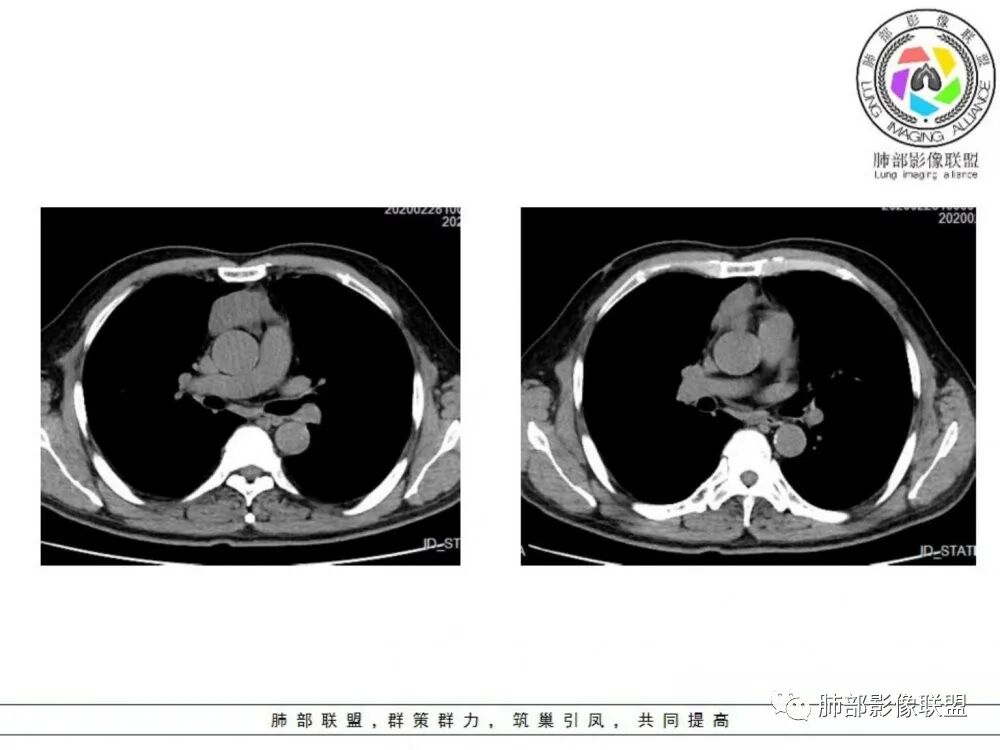

男性患者,65岁,前胸后背疼痛一个月。影像学前上纵隔分叶状的软组织肿块,肿块形态怪异,偏软,位于大血管间隙前,并有向血管后间隙发展的趋势,平扫CT值为40左右,增强扫描中心部未见强化,周围轻度的强化,约为50左右。前上纵隔的疾病谱包抬胸廓内甲状腺肿、胸腺瘤/癌、畸胎瘤、淋巴瘤。少见的心包囊肿或支气管囊肿。根据肿块的形态及强化特点,首先还是排除了胸内甲状腺肿及胸腺来源的肿物,这类的肿物强化比较明显。畸胎瘤成分比较复杂,具有软组织钙化或者脂肪类的组织,这个肿物虽然在平扫的时候好像有斑点状的钙化灶,但是总体成分还是比较单一,所以还是排除畸胎瘤的诊断。所以这样的情况是考虑:淋巴类的肿瘤,注意排除心包的囊肿或支气管来源的囊肿。

老年男性患者,前膈软组织肿块,边缘轮廓不光整,边界似乎尚清晰,内见小点状钙化灶,平扫密度欠均匀,增强后轻度强化表现,边缘有些斑片状的高强化区。综合考虑胸腺瘤或胸腺鳞癌,神经内分泌癌强化弱了一些。患者年龄较大,生殖细胞肿瘤不考虑,淋巴瘤血管包绕不够,可能性不大

临床,老年男性,病史一月。1 定位,骑跨大血管,大部分位于胸腺区域内,周边部分胸腺脂肪有混浑浊,起源于胸腺区的组织应该没有问题。2 定性 。恶性征像,分叶,大血管侵润,pet高代谢,左侧庄层胸膜增厚(类似脑膜瘤的脑膜尾征,良性表现?)。良性征像,病灶均匀,无明确坏死?综合恶性征像多些,考虑恶性可能大。病灶分两部分,部分层面似有明确分割,两个性质的病灶长一块,还是,一个病灶两种不同成分?一个病灶伴均匀坏死?CT值41hu,坏死好像高了点,一个病灶,相同成分,只是血管分布不同,增强是持续流入型强化。纤维类?编不下去了,岔路太多,祭出法宝按概率蒙吧:侵袭性胸腺瘤>神经纤维瘤>乏血供CD

老年男性,前纵隔不规则软组织肿块影,密度欠均匀,与大血管分界欠清,上腔静脉局部包绕受侵,增强扫描不均匀轻度强化,PET-CT高代谢。考虑恶性肿瘤性病变,胸腺癌可能。鉴别淋巴瘤。

中老年男性,前纵隔占位,基本居中,向两侧生长;边缘膨隆分叶,部分边界不清,增强不均匀轻中度强化,坏死区边界不清;周围多发增大淋巴结,考虑恶性。主要在胸腺癌、胸腺瘤、淋巴瘤之间鉴别。病灶偏软,有钻缝样生长,这些征象偏向于淋巴瘤。但此例老年患者,病灶内有点状钙化,缺乏结节堆砌感,倾向胸腺癌诊断。

1、淋巴瘤:年龄跨度大,多发淋巴结肿大,融合成团,轻中度强化,约1/3可见胸腔、心包积液。多结节融合是其特点,多伴有中纵隔淋巴结肿大,包绕血管。

2、侵袭性胸腺瘤:肿块与纵隔诸器官脂肪间隙消失,血管变形移位,可见心包积液,胸膜受累类似胸膜间皮瘤。